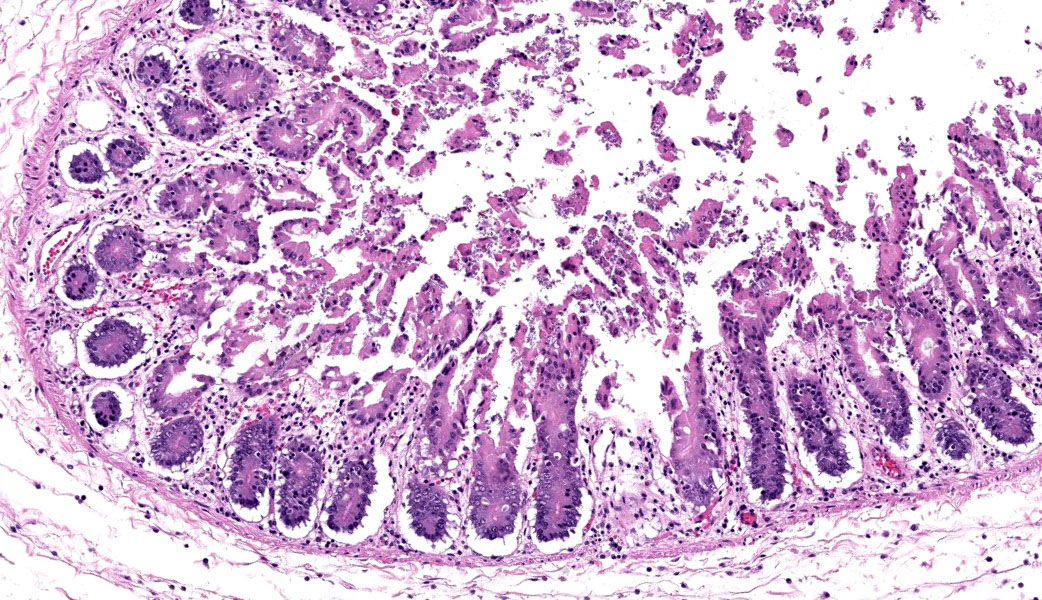

Cecum at ileocecocolic junction: One full-thickness cross sections of cecum at the ileocecocolic junction are examined from each animal (2 total). Diffusely, the submucosa is expanded by clear space (edema) and admixed inflammatory cells (neutrophils, macrophages, lymphocytes, and fewer plasma cells). The lamina propria is multifocally expanded by edema, hemorrhage, the previously mentioned admixed inflammatory cells, and karyorrhectic debris. The overlying epithelium has multifocal erosions and ulcerations with surface necrotic debris and mixed bacterial colonies.

Colon: Colitis, necrotizing, subacute, multifocal, moderate, with volcano lesions, hemorrhage, and severe submucosal edema.

Similar to Case 1, due to the presence of volcano lesions coupled with mucosal ulceration/necrosis and heterophilic inflammation, Dr. Uzal says this is C. difficile until proven otherwise! This case had some solid examples of volcano lesions in which heterophils could be seen exploding out of tiny ulcers in the mucosa.